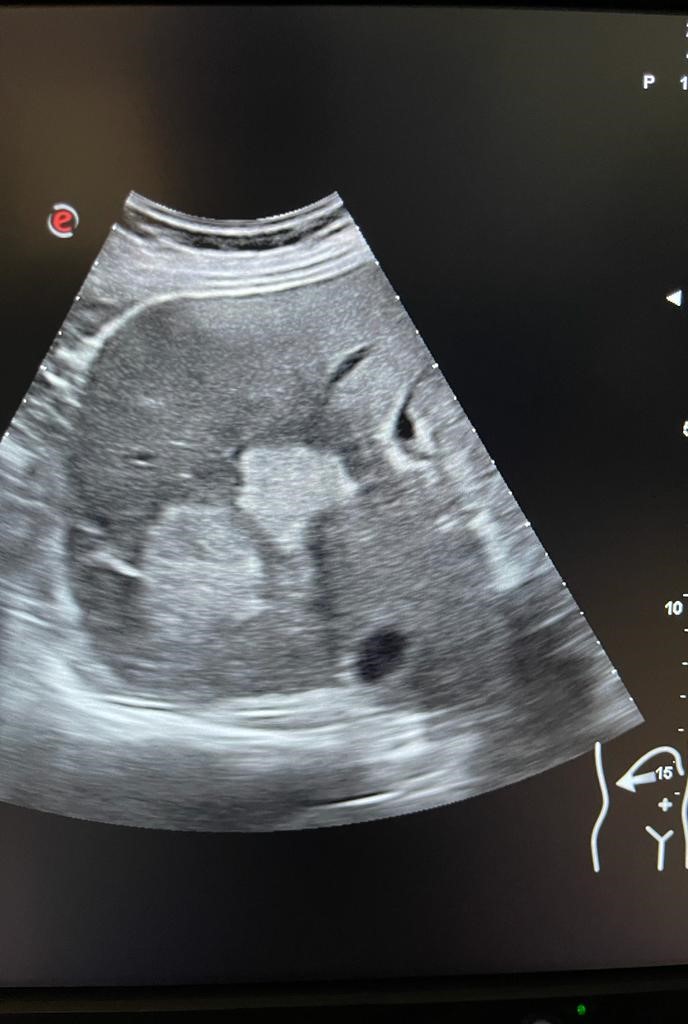

Se aprecia hígado heterogéneo con múltiples LOES hepáticas hiperecogénicas (una de ellas de unos 7x7 cm), sin captación de doppler. Al menos otras 2 LOES de menor tamaño presentan halo hipoecoico. Vesícula replecionada de contornos lisos y sin litiasis en su interior. Ambos riñones visualizados de tamaño normal y sin datos de hidronefrosis.